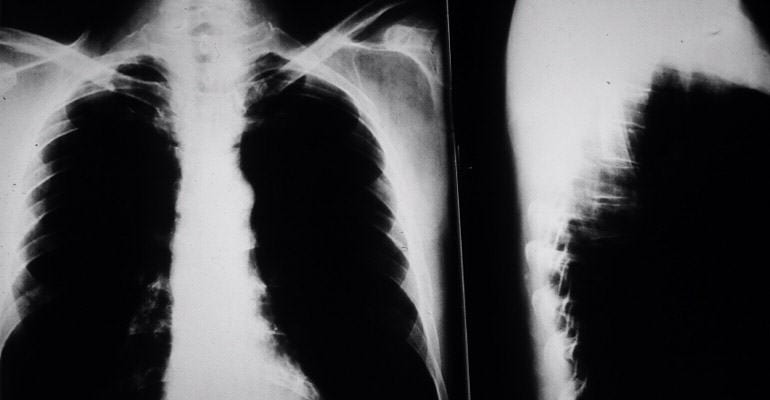

If an asbestos fiber is inhaled or swallowed during exposure, it can become lodged in a person’s mesothelium, a lining that protects the lungs and other internal organs.

3 out of 4 cases of mesothelioma begin in the pleural mesothelium surrounding the lungs, but it can also begin in the abdominal cavity or around the heart.